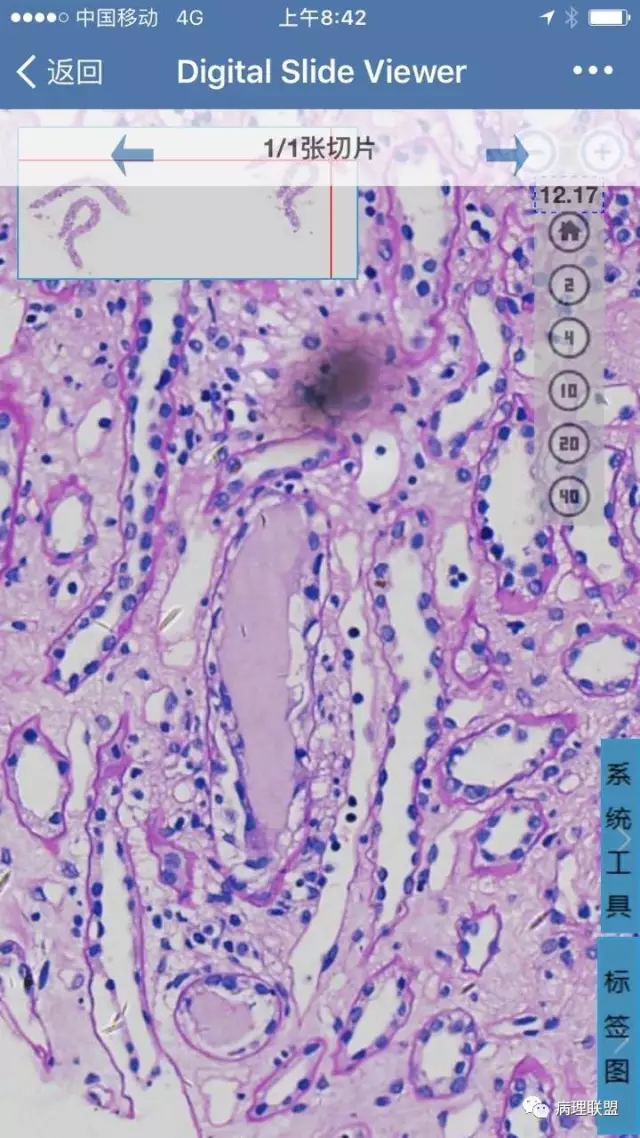

因患者主要是肾功能变化,光镜下除了少数肾小球硬化,其余肾小球病变较轻,免疫荧光阴性,所以报告就按照急性肾小管-间质损伤发了,后来临床反馈患者有骨髓瘤病史,经仔细寻找,在肾髓质远端小管内发现极少量PAS染色很淡的管型。

在数字切片中需要仔细寻找才能找到这个部位